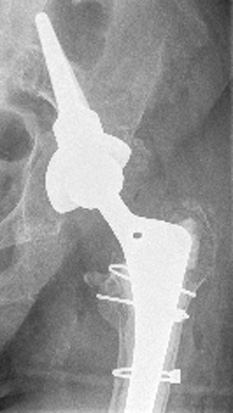

Bei der operativen Behandlung der periprothetischen Fraktur soll aufgrund des meist fortgeschrittenen Alters des Patienten auf jeden Fall eine frühe Mobilisation möglich sein. Wir verfolgen daher das Ziel, durch eine geeignete Technik eine Vollbelastung ab dem Operationstag zu ermöglichen (frühfunktionelle Mobilisation).

Daher versorgen wir periprothetische Knochenbrüche mit winkelstabilen Platten (operative Osteosynthese). Diese weichteilschonenden Platten verbinden die Bruchstellen und stabilisieren sie. Wenn die Prothese bzw. der Prothesenschaft selbst nicht gelockert ist, genügt die Stabilisierung der Bruchstelle durch Platten.

Bei einer Lockerung des Prothesenschaftes wird zusätzlich die Prothese ausgetauscht. Ein solcher Prothesenwechsel muss schnell für Belastbarkeit sorgen und gleichzeitig die Hüftprothese langfristig stabil befestigen.